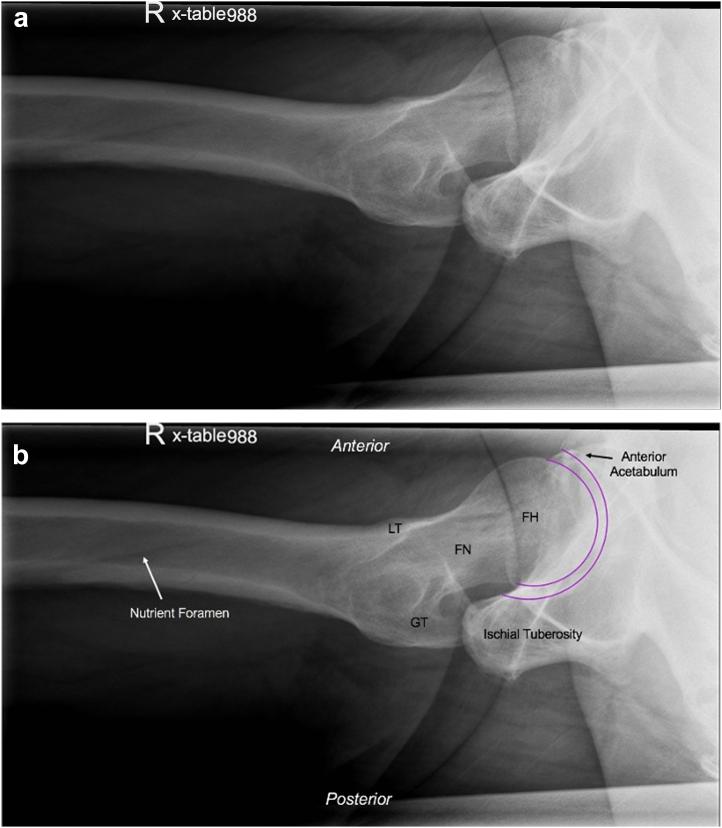

The specialty evaluation of hip pain, stiffness, and/or dysfunction usually includes patient history, physical examination, and radiographic evaluation. Radiographic views of the hip are not standardized, and basic studies may include an anteroposterior pelvis, anteroposterior hip, frog lateral, and direct lateral of the hip. In this article, we discuss the importance of obtaining a direct lateral radiograph of the hip in all patients being evaluated by a specialist for hip pain and its value in hip arthroplasty care.

对髋部疼痛、僵硬和/或功能障碍的专科评估通常包括患者病史、体格检查和影像学评估。髋部的影像学检查视图并不标准化,基础检查可能包括骨盆前后位、髋关节前后位、蛙式侧位和髋关节直接侧位。在本文中,我们讨论了在所有因髋部疼痛接受专科评估的患者中获取髋关节直接侧位X线片的重要性及其在髋关节置换术治疗中的价值。